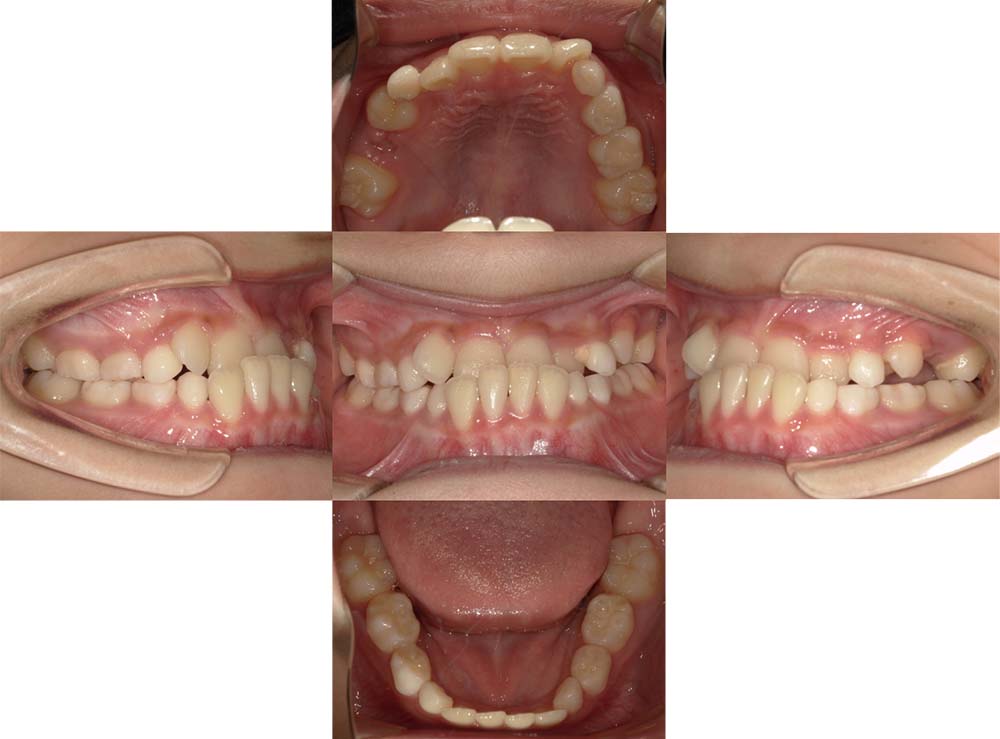

症例04

| 主訴 | 歯並びのガタガタと出っ歯が気になる。 |

| 診断名あるいは主な症状 | 上顎前突、叢生 |

| 年齢/性別 | 16歳・女性 |

| 矯正ステージ | 大人の矯正治療 |

| 治療方法 | ワイヤー矯正 |

| 抜歯部位/抜歯有無 | 抜歯 |

| 治療内容 | 抜歯したスペースを使用し、ガタガタの改善と上下顎前歯を後退させた。 |

| 費用 |

85万円程度(2025.10時点の料金となります。) ※矯正基本料金、審美ブラケットを含む |

| 治療期間 | 2年5ヶ月 |

| 主なリスク・副作用 | 痛み、歯根吸収、歯肉退縮、虫歯、後戻り |